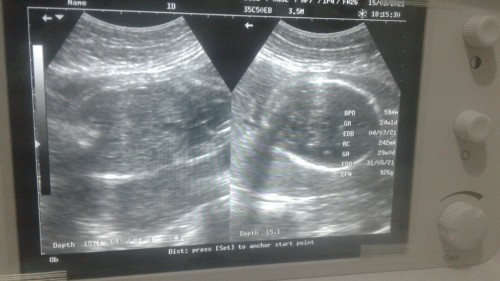

Usia kandungan sudah 8bln 10minggu tapi sama sekali belum menyiapkan keperluan si dedek 😣.. suwami bingung haru gimana kerjaan susah buat makan sehari" sudah ada alhamdulilah, , tpi iri lihat orang" yng baru 7bln udah lengkap buat dedeknya Semoga aja sebelum hari H bisa beli perlengkapan baby amin" #bantusharing #jangandibully